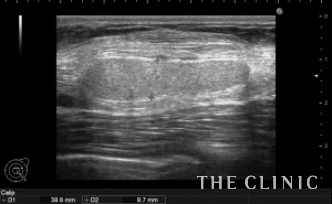

左胸に4㎝弱のしこりが触れ、エコーでは充実性のしこりでした。

さらに1ヵ月経過後のエコーです。

黒いオイル成分が増えてきましたので、太めの注射針で穿刺吸引しました。